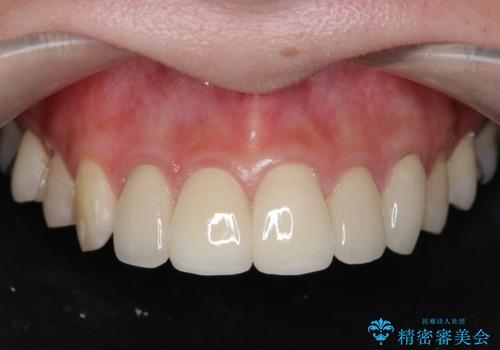

- 数ヶ月前に他院で装着したセラミッククラウンから、歯ブラシのたびに出血することの改善を求めて来院されました。

X線写真よりクラウンの際があっていない状態であることがわかり、再度精度の良いセラミッククラウンを製作していくこととなりました。

- 22万円(仮歯・ジルコニアクラウン×2)費用は治療当時の料金となります